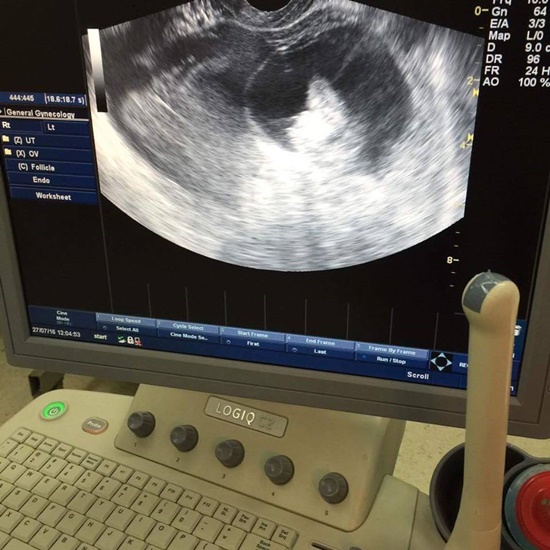

สาวโพสต์เรื่องราวอุทาหรณ์ หลังเข้าใจผิดว่าก้อนเนื้อที่ท้องเป็นไขมันจนปล่อยไว้นานไม่ยอมไม่ไปตรวจ สุดท้ายทนไม่ไหวตรวจพบเป็นเนื้องอกในรังไข่ขนาดใหญ่กว่า 20 เซนติเมตร

แต่พอผ่านไปไม่นานตนรู้สึกท้องเริ่มใหญ่ขึ้น ท้องอืด ถ่ายยากขึ้น และปัสสาวะแสบขัด เวลาวิ่งจะรู้สึกมีก้อนอะไรอยู่ในท้องแน่ จึงยอมไปตรวจและพบว่าตนเองมีเนื้องอกในรังไข่ ขนาด 13 เซนติเมตร โดยระหว่างรอเข้าห้องผ่าตัดประมาณ 1 เดือน ตนมีอาการปวดท้องมาก จนกระทั่งวันที่ 9 กันยายนที่ผ่าน คุณหมอได้ทำการผ่าตัดให้และพบว่า ก้อนเนื้อมันแตกตั้งแต่อยู่ในท้องมีขนาดใหญ่กว่า 20 เซนติเมตร ทั้งยังต้องถูกตัดปีกมดลูกและรังไข่ด้านขวา รวมทั้งตัดต่อมน้ำเหลืองเชิงกรานออกด้วย เพื่อลดการแพร่กระจาย รวมทั้งก้อนเนื้อโตไวมาก ดังนั้นตนจึงอยากเตือนทุกคนให้ช่วยกันสังเกตตัวเองเป็นประจำ